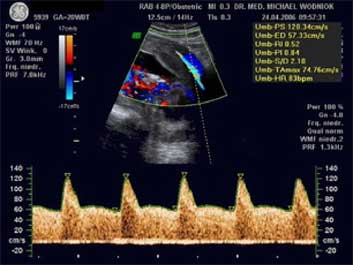

Unterscheidung zwischen dem anlagebedingt kleinen (nicht gefährdeten) und dem minderversorgten (gefährdeten) Kind. Der Nachweis einer chronischen Mangelversorgung des Kindes durch eine nicht ausreichende Funktion des Mutterkuchens (Plazenta) gelingt mit der Dopplersonographie durch die Messung der Blutströmungsverhältnisse in der Nabelschnurarterie und Gehirnarterie des Kindes mit de Dopplersonographie.

Zusammengefasst ist die Dopplersonographie ist eine Art Frühwarnsystem. Denn krankhafte Veränderungen beim CTG (Herztonaufzeichnung des Kindes) treten etwa erst 10-14 Tage nach den ersten Auffälligkeiten in der Dopplersonographie auf. Liegt ein Risiko gemäß den Mutterschaftsrichtlinien vor, wird die Doppleruntersuchung von uns zu Lasten der GKV abgerechnet.